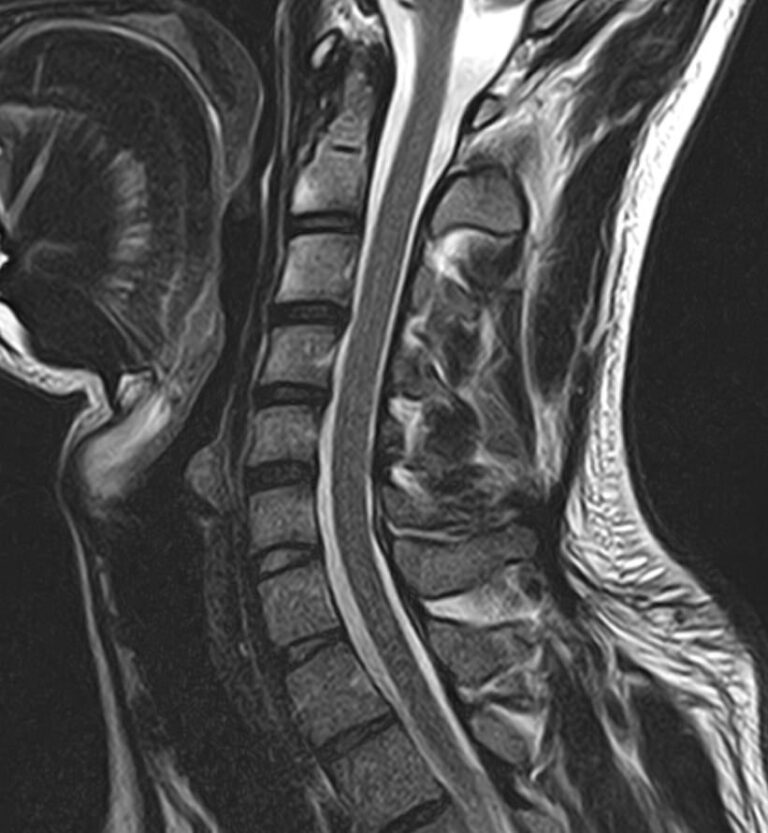

Шейный отдел позвоночника — это самый подвижный сегмент позвоночного столба, который испытывает повышенные нагрузки, подвержен травмам и развитию различных заболеваний. В эту анатомическую область входит 7 верхних позвонков, спинной мозг с отходящими от него нервными корешками, а также проходят крупные сосуды, кровоснабжающие головной мозг.

МРТ шейного отдела позвоночника позволяет проводить диагностику дегенеративных заболеваний позвоночного столба (в том числе межпозвонковых грыж, протрузий, остеохондроза), выявлять воспалительные, травматические изменения и объемные образования в области шейных позвонков и спинного мозга.

В клинике «Доступная медицина» данное исследование проводится на современном высокопольном магнитно-резонансном томографе экспертного класса TOSHIBA VANTAGE TITAN 1,5 Тесла. Напряженность магнитного поля 1,5 Тесла обеспечивает высокую разрешающую способность аппарата, что позволяет выявлять минимальные изменения в тканях и диагностировать заболевания на начальной стадии.

МРТ шейного отдела позвоночника позволяет выявить практически любые изменения в костных и мягких тканях. Исследование характеризуется высокой результативностью при следующих нарушениях:

• остеохондроз шейного отдела позвоночника;

• грыжи межпозвоночных дисков;

• компрессия спинномозговых корешков и спинного мозга;